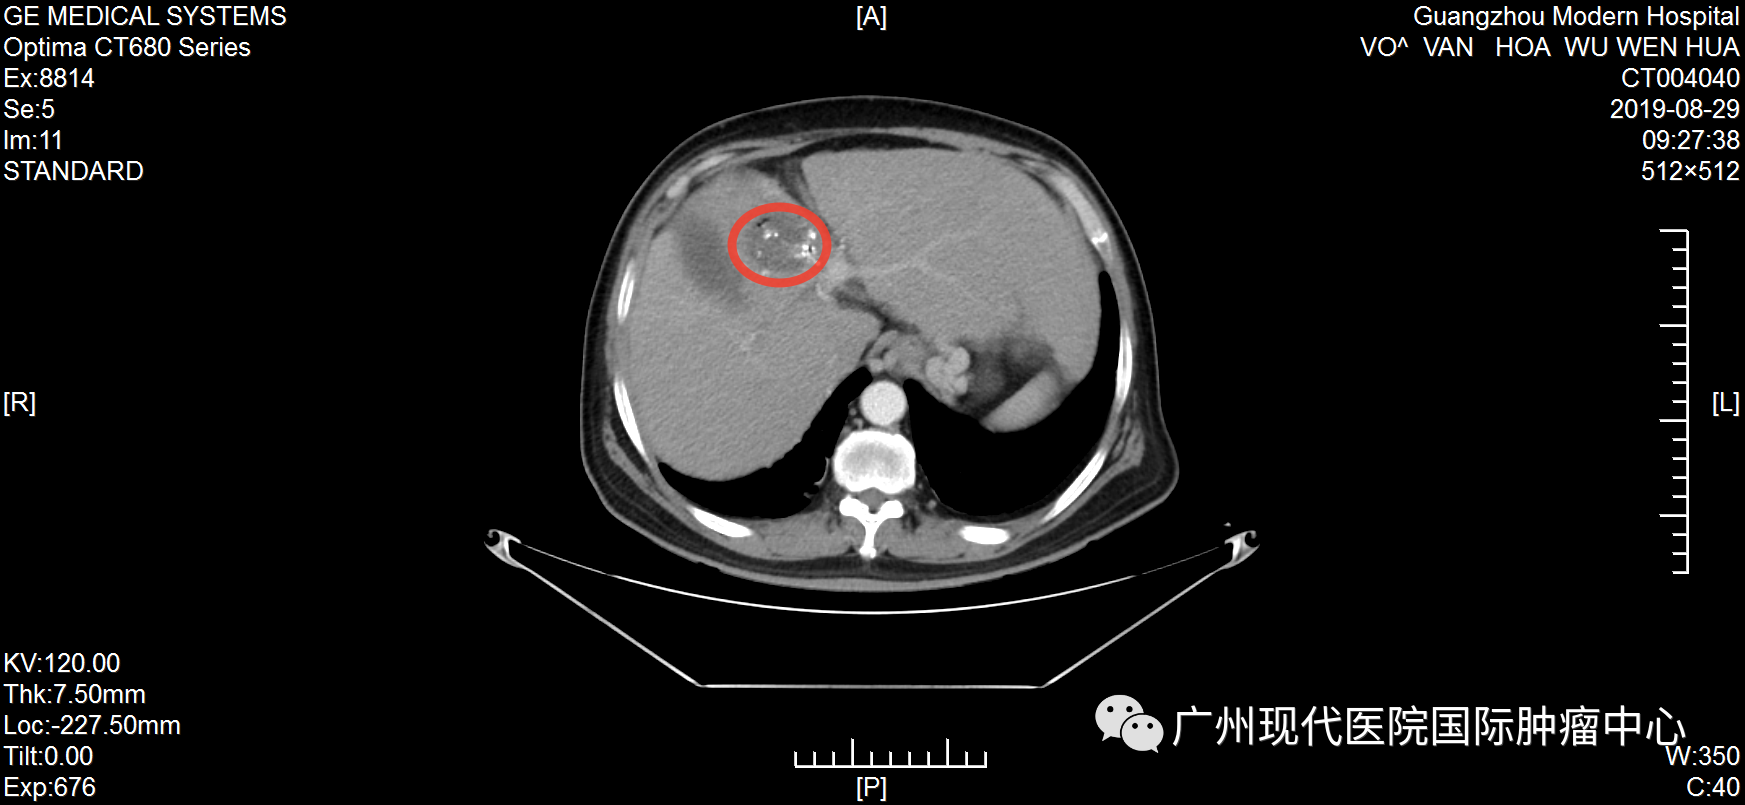

不愿做手术, 弟子推荐好医院 武文华自10岁起出家,年轻时,一直去各大佛寺学习佛教知识和游历,直至1999年时确诊丙肝,此后一直坚持吃药治疗。不曾想,时间的指针转到2019年,丙肝恶化为肝癌。 2019年6月,武文华因反复劳累出现低热,伴随右上腹胀痛、头痛等症状,且面部神经受影响,尤其是下颌与唇部麻痹且疼痛。随后,他到当地医院就诊,做腹部CT检查,初步诊断为肝细胞肝癌、肝硬化。当地医生建议做手术,武先生不愿意开膛破肚,也担心手术风险、术后感染等问题,于是拒绝越南医生的治疗方案。 武文华和妹妹及弟子合影 机缘巧合下,武文华的弟子了解到自己的一位亲友在一家口碑很好的癌症专科医院——圣丹福广州现代肿瘤医院获得了很好的治疗,现在肿瘤已经完全消失了。弟子把这家医院推荐给武文华,告诉他不用开刀也能很好地治疗癌症,并给他介绍最新的微创技术。“不用开刀”这一技术优势深深地吸引了武文华,他很快找到胡志明办事处咨询,并在工作人员的帮助下来到广州。 微创综合治疗, 让他重获新生 2019年7月,武文华来到圣丹福广州现代肿瘤医院。根据他的病情,医院MDT医疗团队研讨决定,给予他综合微创治疗方案。 第一次住院期间,武文华先后接受介入治疗、纳米刀等微创治疗。介入治疗可以切断癌细胞营养供给,抑制肿瘤生长,减少肿瘤转移,直至彻底杀死肿瘤;而纳米刀是一种全新的尖端肿瘤消融技术,通过电极探针释放高压脉冲击穿肿瘤细胞的细胞膜,形成多个纳米级不可逆的电穿孔,破坏细胞膜,从而破坏癌细胞组织,使细胞快速凋亡。他曾经的主治医生马主任表示,这个治疗方案,非常适合武文华这种不愿接受传统治疗、甚至对放化疗已经产生耐受性的癌症患者。 2019年武文华住院期间生活照 据了解,入院前,武文华体内的肿瘤大小为70*60mm。经介入栓塞治疗和纳米刀治疗后,肿瘤缩小到22*16mm。回忆治疗过程,武文华表示:“因为不需要开刀,每一次微创治疗都在半小时内结束。做介入治疗时,没有任何痛感,第二天就可以下床。纳米刀是在全麻的情况下做的,没什么感觉。” 治疗1个月后,肝部肿瘤明显缩小 治疗5个月后,肿瘤已基本消失 活动中,马主任回忆称:“他总共接受了5次介入治疗和纳米刀治疗,综合治疗完成后,肝部的肿瘤基本消失,他头痛发烧及面部神经影响等问题也得到了解决。”肿瘤消失后,为了巩固治疗效果,他遵守医嘱再次入院并接受了免疫治疗。 自2019年7月至今,武文华已经抗癌成功5年了,这对于他的家人而言是一种莫大的幸福。他的妹妹欣喜地说:“此前在越南的医院,医生下结论说他不做手术只能活3个月,如果做手术成功率只有30%。时间证明我们选择来广州治疗是对的,现在他每年仍然在越南定期检查,结果完全稳定,而健康的状态现在已经延长了5年,这是一个奇迹!” 医患情暖人心, 定下十年之约 这是武文华第三次回到医院。在采访中,他表示:“我完成治疗返回越南后,新冠疫情就爆发了,我像往常一样进行寺庙的日常管理工作,还积极参加抗疫的工作,我很幸运能够那么快地恢复健康,这要归功于医院的精心治疗和护理。” 住院期间,因为面部神经不适等症状,武文华被我院医护人员悉心照料照顾,他为之动容并为他们创作了一首诗:“别时合影它日忆,此处高风妙可夸。天使殷勤通昼夜,良医吐哺映莲花。”谈起写诗的初衷,他说:“我曾经在别的医院治疗过,后面依然选择这里,是因为这里的医生和护士都非常专业,对病人热情而周到。” 2019年,武文华出院时为我院赋诗及合影 活动中,武文华和主治医生马主任合影 他以亲身经历,对其他患者强调,肿瘤不是一种绝对导致死亡的疾病,而是一种慢性病。“现在我能够正常地饮食,工作,还能进行体育锻炼。如果你确诊了癌症,请不要灰心,不要悲伤,一定要遵守医嘱,相信自己可以恢复健康。” 抗癌明星的聚会中,马主任仔细聆听他的分享,不断绽放出感动与欣慰交织的笑容。她难掩心潮澎湃,还定下一场“十年之约”:“看到武大师目前拥有这么健康的状态,我感到我们医护人员所有的努力和付出都是值得的。希望十年后和大家再相聚!” 活动后,武文华还同其他抗癌明星们一起,体验了一场精彩纷呈的广州之旅。他们夜游珠江,体验现代都市的繁华;结伴同游宝墨园,观中华文化的博大精深。他们的癌后余生,正如脚下的路,徐徐绵延向前,充满阳光! 微创治疗技术简介 纳米刀:是一种全新的肿瘤消融技术,源于不可逆电穿孔技术,通过电极探针释放高压脉冲击穿肿瘤细胞的细胞膜,形成多个纳米级不可逆电穿孔,破坏细胞内外平衡,使细胞快速凋亡。治疗优势是时间短、 治疗区域的血管、神经等重要组织得以保留、安全可靠等。 1、具备创伤小、并发症少、安全、恢复快的优势。 2、可适应更多复杂的病情,包括胰腺、肝、肺、肾、前列腺以及其他实体肿瘤 介入治疗:在医学影像设备引导下穿刺,利用特制导丝等精密器械,将比静脉点滴药物浓度高2~8倍的抗肿瘤药物直接注入肿瘤内部,同时对肿瘤的供血动脉进行栓塞,实现肿瘤缩小甚至消失的目的。 1、具备创伤小、并发症少、安全、恢复快的优势。 2、适合采用传统放化疗效果不佳、不愿或不适合做手术等情况的患者。